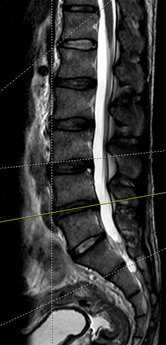

主诉:腰部疼痛1年余,伴左下肢疼痛麻木3月。 病史:女性患者,53岁。患者1年余前在做家务时出现腰部剧烈疼痛,当时腰部活动受限,在外院门诊诊断为腰肌劳损,给予对症治疗,效果较好。1年余来活动后腰部均出现疼痛,反复出现。最近3年以来,患者腰部疼痛时间延长,加重,并伴左下肢麻木,放射痛至足踝处。患者一般情况尚可。

查体:腰4/5、腰5/骶1棘间及左右棘旁轻压痛、叩击痛,左侧坐骨神经出口处明显压痛。左小腿外侧感觉略减退,左侧伸膝、踇背伸肌力4级,左侧直腿抬高试验20°(+),加强(+),Lasegue征(+),左侧4字征(+),左侧股神经牵拉试验(+)。双侧Babinski 征及Oppenheim 征(-)。 辅助检查:三大常规、血生化、肝肾功能均未见明显异常。患者腰椎动力位片正常,其余重要腰椎影像学如下。

诊断:腰椎间盘突出症(L4/5) 治疗:患者入院后尽快完善相关检查,患者目前腰椎稳定性尚可,暂拟”椎间孔镜微创“治疗。